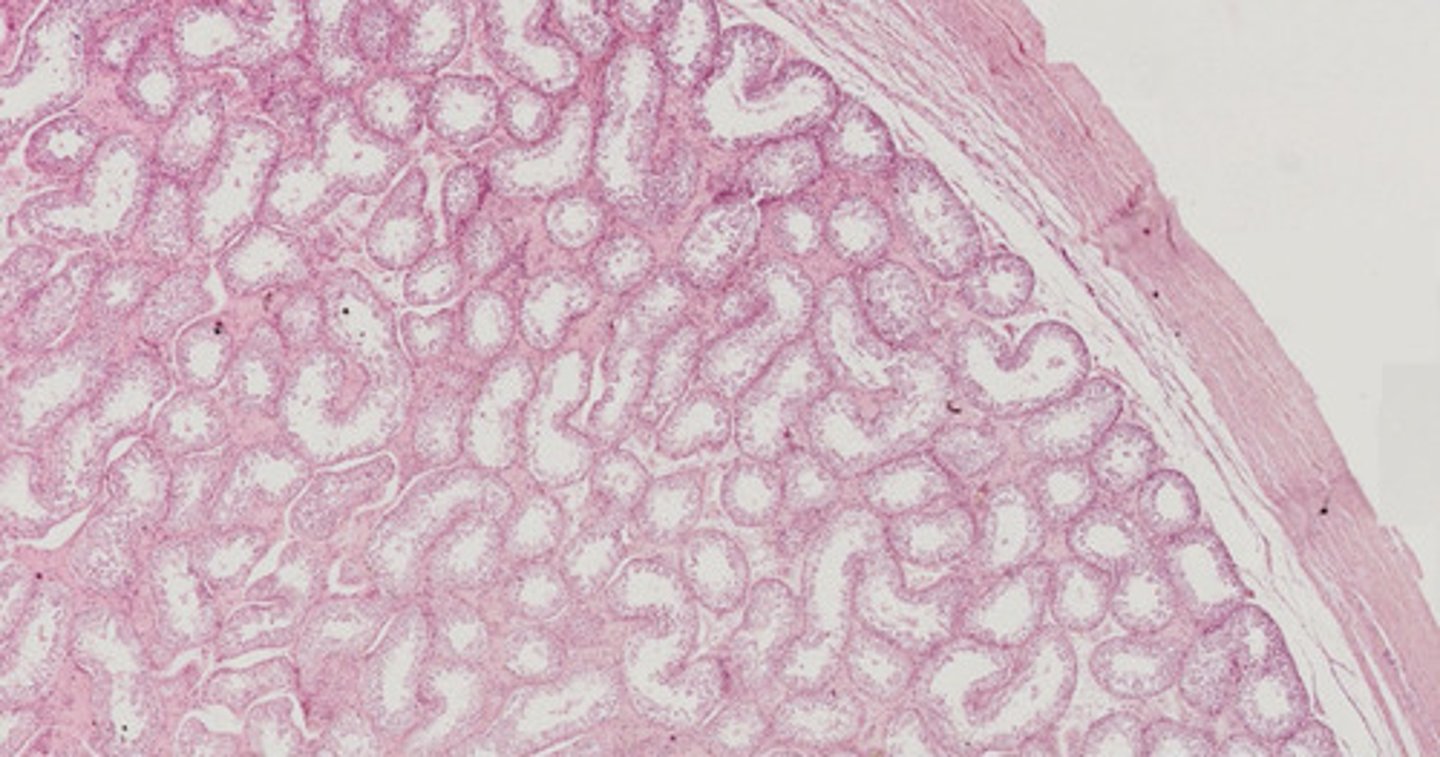

Nerka ludzka; aparat przykłębkowy (H+E)

Nerka nastrzyknięta - obrazowanie naczyń (masa iniekcyjna z błękitem metylu)